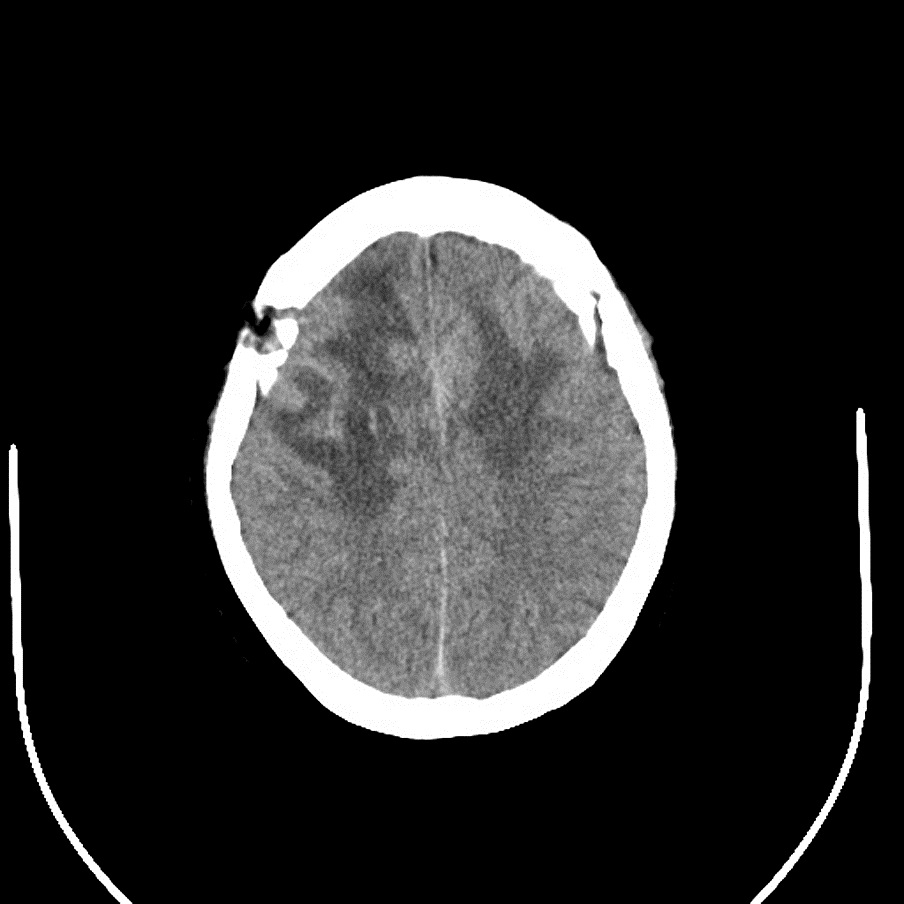

2016年8月,54岁的李某因“双侧大脑镰矢状窦旁巨大脑膜瘤”(直径达6.5厘米)四处求医,诊断明确;却因居住深山区,家庭贫困,支付不起昂贵的医疗费用想要放弃治疗。几经周折,李某最后来到嵩县人民医院神经外科就诊。神经外科医务人员经过全面评估,认为李某具备手术条件。

手术历时13小时(如上图),肿瘤全部被切除,且患者术后无明显的后遗症,得到省市级医院专家的一致认可。这也是嵩县人民医院神经外科具有里程碑意义的一台手术,充分显示了该科的技术实力,取得了较大的社会影响。

手术后   |